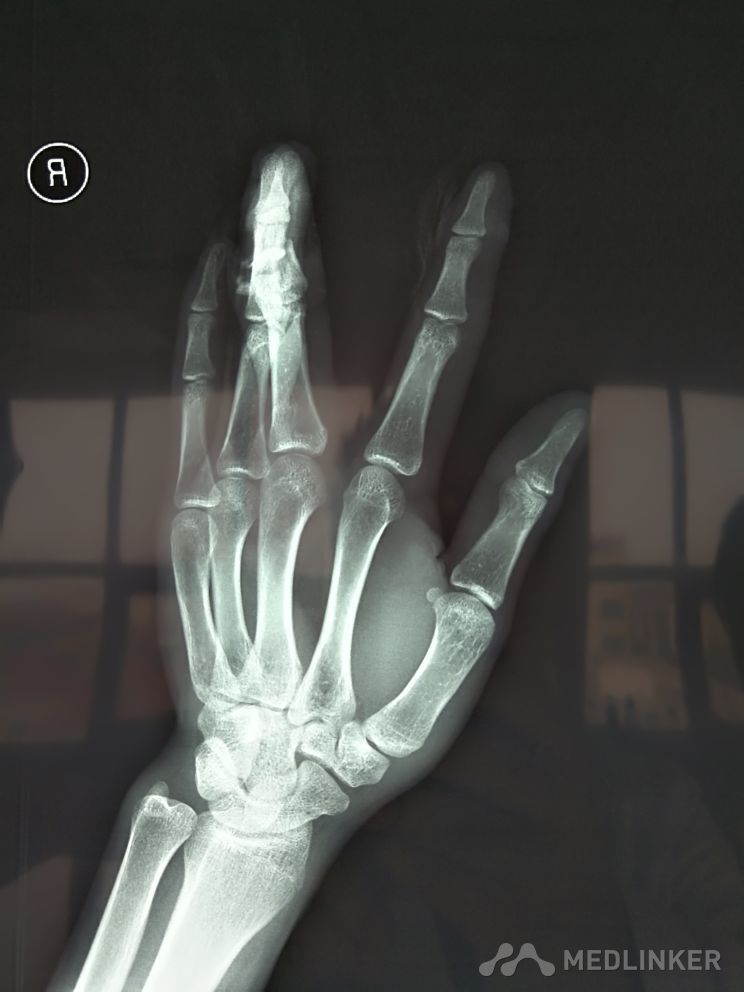

手指粉碎性骨折

患者机器碰伤,导致中指粉碎性骨折,关节面毁损。